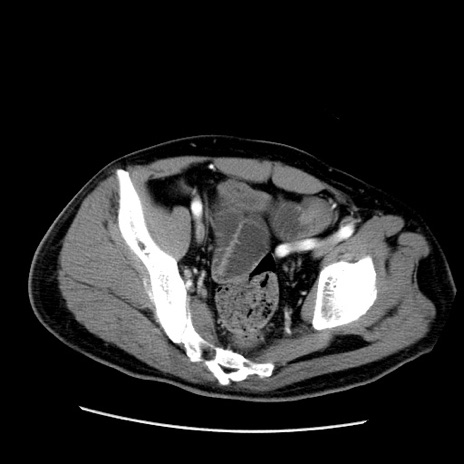

症例22(横断像)

【症例】50歳代男性

【主訴】腹痛

【現病歴】AVMからの被殻出血のため回復期リハ病棟入院中。 本日午後3時頃急に下腹部痛が出現した。

【既往歴】AVM、被殻出血、虫垂炎、高血圧

【身体所見】意識晴明、左半身不全麻痺、会話の理解は良好、36.5°C、腹部:膨隆、全体に板状硬、下腹部正中に圧痛点あり、反跳痛-、筋性防御不明、右下腹部にope scar

【データ】WBC 9400、CRP 0.06